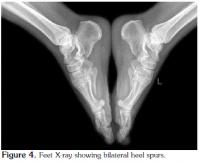

The patient was then admitted for further investigation. From an analytical point of view, there was an increase in acute phase reactants [C-reactive protein (CRP) 95.2 mg/L and erythrocyte sedimentation rate (ESR) 87 mm/hr]. Microcytic anemia was also present (hemoglobin 11.2 g/dL, mean erythrocyte volume 79.4 fl, and iron 37 mg/dl), but the ferritin and serum levels were normal as were the total iron binding capacity and transferrin saturation rate. Serum protein electrophoresis revealed a decrease in albumin (47.3%), whereas the alpha 1 (16.1%), alpha 2 (14.9%), and gamma globulin (21.3%) levels were higher. Other immunological tests determined that the rheumatoid factor (RF), anticyclic citrullinated peptide (anti-CCP), antinuclear antibody (ANA), complement, and anti-doublestranded deoxyribonucleic acid (anti-dsDNA) levels were normal, and the serum uric acid levels were also within normal limits. Furthermore, the primary and secondary tuberculosis screening tests were negative, and the serology tests for Brucella, Chlamydia, the human immunodeficiency virus (HIV), and hepatitis B and C were negative as well. Human leukocyte antigen typing revealed the presence of A1, A2, B41, B57, Cw6/7, DR11, and DR13 while a urinary system ultrasound and an intravenous pyelogram were normal. An X-ray of the pelvis showed degenerative changes (Figure 1), and because of the patient's ongoing lower back pain and peripheral joint swelling, magnetic resonance imaging (MRI) of the sacroiliac joints was performed, which showed periarticular edema of the sacrum in the anterior segment along with a slight increase in sclerosis of the right sacroiliac joint in the anterior superior segment. Slight edema of the left periarticular sacral area was also seen in the posterior segment. We then recommended that the MRI findings be interpreted in accordance with the clinical picture.